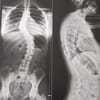

Double scoliose de 45 degres

Je suis suis une fille qui va avoir 16ans dans 4 mois .Moi même suis atteinte d'une scoliose ,j'ai 45 en bas et 37 deg en haut .elle a été découverte en 2012 et j'ai porté un corset pendant 3 ans ce qui a été l'enfer pour moi .(je l'ai arrêté en août 2017 donc il n'y a pas très longtemps .) mais mon chirurgien m'a dit que j'étais à la limite de me faire opérer donc je le revois que dans 8 mois(et si je vous disais que j'aimerais me faire opérer vous diriez quoi ? Me comprendrez vous ? ) . Par ailleurs je fais du water-polo un sport d'eau depuis 2 mois voilà mon histoire !